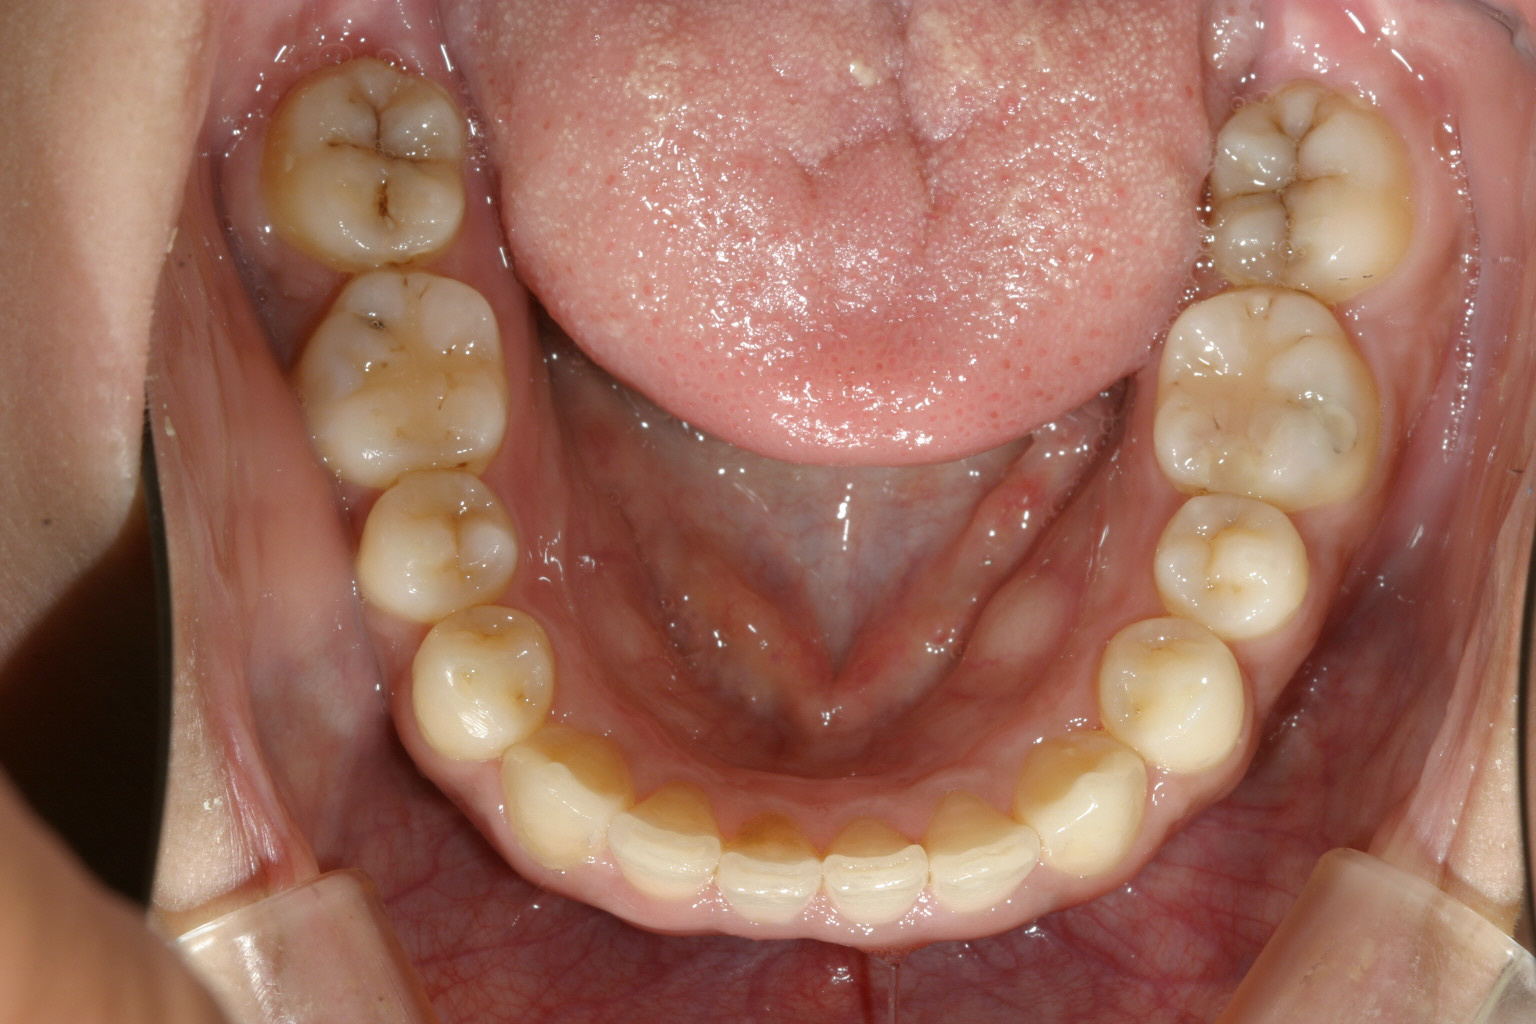

マルチループを装着5ヵ月後です。殆ど綺麗に改善しています。

下顎は殆どすでに改善しています。